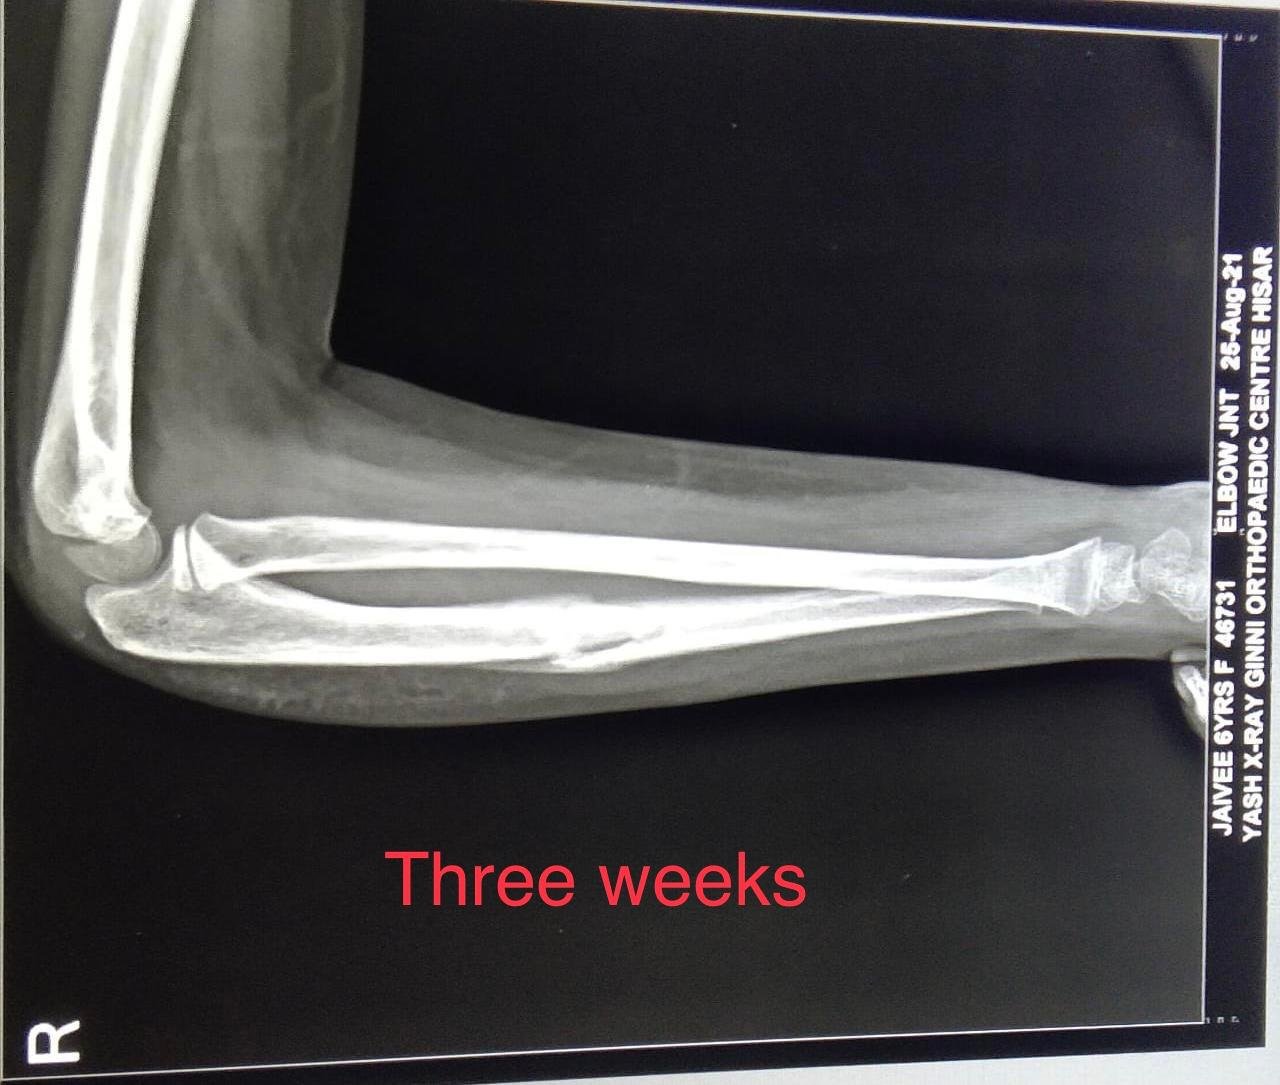

• X-ray: To classify the fracture

• Regular follow-ups with imaging